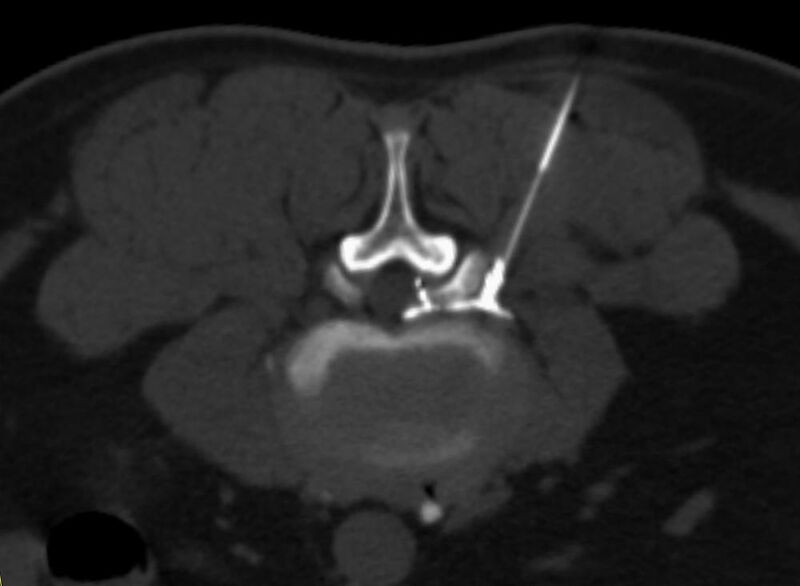

Interventionelle Eingriffe

Durchführung am Standort im Diakonissenkrankenhaus

• z. B. Punktionen zur Gewebsentnahme

Schmerztherapie

(dazu mehr auf der Seite Schmerztherapie)